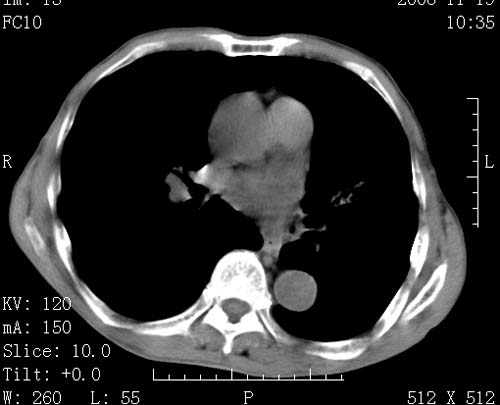

标题: CT16691:m 67 胃镜确诊食管下段及贲门癌 [打印本页]

标题: CT16691:m 67 胃镜确诊食管下段及贲门癌

术前查体,双肺部结节是转移?结核?请点评

转移 隆突下淋巴结亦肿大

首先考虑转移,纵隔内淋巴结亦肿大;

1)符合食管癌表现。2)两肺及纵隔淋巴结多发性转移瘤。3)左肺上叶舌段及两肺下叶炎症感染。